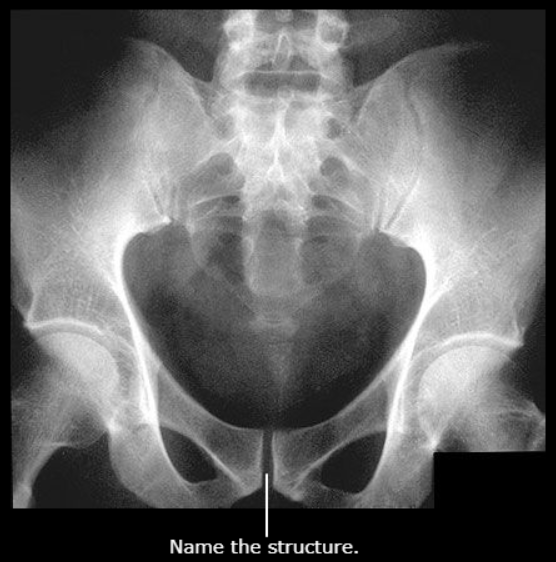

Pubic Symphysis